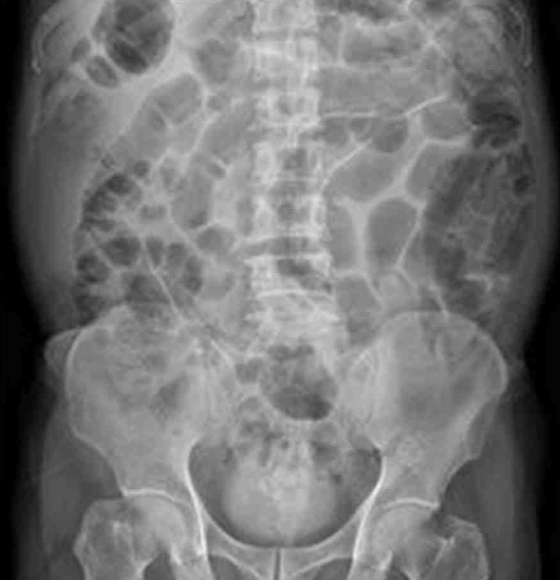

AXR: Gaseous bowel distension

• AXR상에선 gas retention 및 bowel dilatation 소견이 관찰되는데, P/E에서 장음이 감소되어 들리는 것과 종합하여 생각할 때 ileus가 병발한 것으로 의심된다. 췌장의 염증은 복강 내 염증을 유발하여 장마비를 유발할 수 있으므로 췌장의 염증으로 인한 장마비 가능성을 생각해 볼 수 있다.